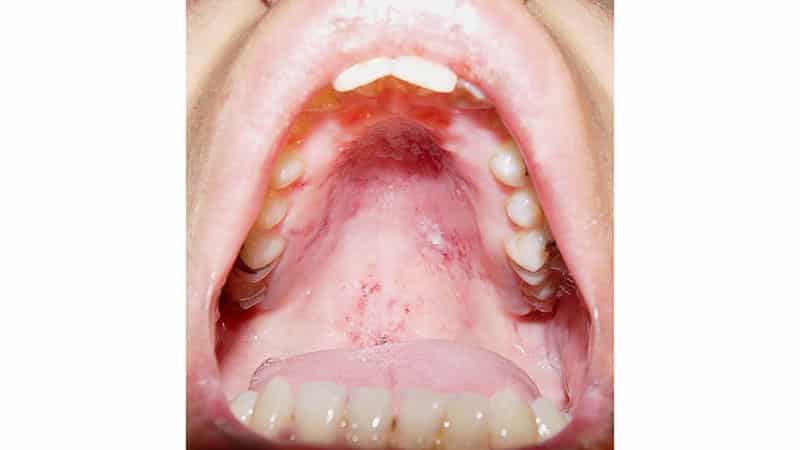

Стоматит представляет собой воспалительный процесс, который проявляется в виде язв на небе во рту (фото различных форм можно найти в нашей галерее). Часто также наблюдаются пятна на языке, деснах и внутренних поверхностях щек. Этим вопросом занимается стоматология. Причины возникновения стоматита могут быть разнообразными:

ХАРС

Наименование данного заболевания связано с его характерным признаком – афтой. Это небольшая язва, которая может появляться на небе, внутренней стороне губ, щеках или деснах, и выглядит как белое пятнышко, окруженное красной воспаленной тканью. Термин «рецидивирующий» указывает на то, что стоматит данного типа проявляется периодически, от одного до трех раз в год. При этом у детей такие рецидивы происходят значительно чаще, чем у взрослых.

По статистике, около 20% населения планеты сталкиваются с афтозным стоматитом ежегодно. Эти язвы, представляющие собой белые точки на небе, могут быть довольно болезненными, а у детей заболевание часто сопровождается общим недомоганием, потерей аппетита, слабостью и повышенной температурой. В большинстве случаев афтозный стоматит проходит самостоятельно в течение двух недель. К сожалению, на данный момент не удается установить точного возбудителя этого заболевания.

Отличительной чертой герпетической инфекции является внешний вид язвочек: они представляют собой небольшие пузырьки с жидкостью, которые могут образовываться на небе, губах или щеках (обычно их много). Дети, как правило, переносят эту инфекцию гораздо тяжелее, чем взрослые.